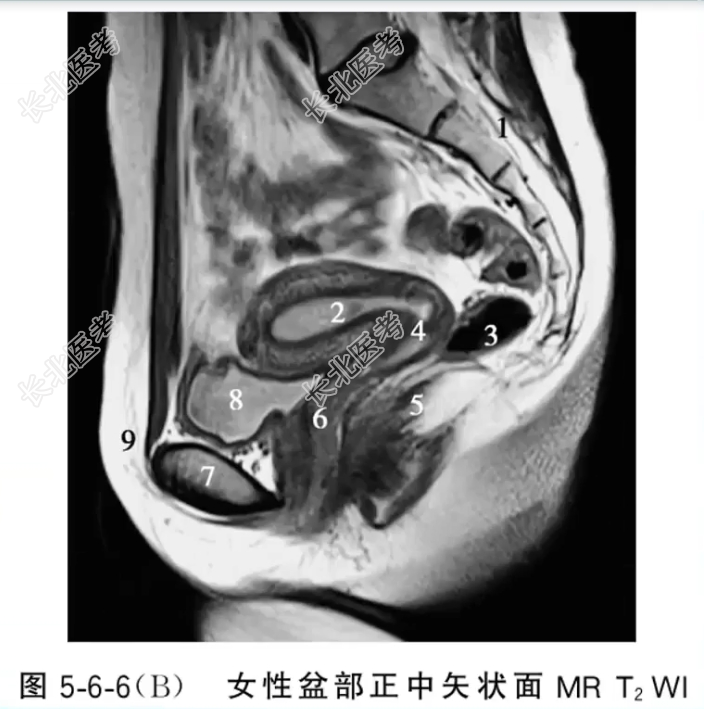

- 单项选择题女性盆部正中矢状面MRT2WI图像中,标记为2、4、6的结构分别是

A、子宫颈、子宫腔、阴道

B、子宫腔、阴道、子宫颈

C、子宫腔、子宫颈、阴道

D、阴道、子宫颈、子宫腔

E、子宫颈、阴道、子宫腔